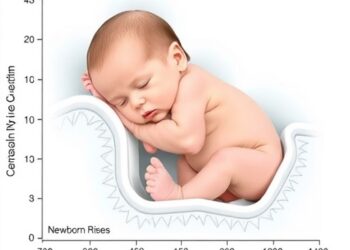

Postnatal Bilirubin Rise Predicts Newborn Health

In the ever-evolving landscape of neonatal medicine, a groundbreaking study has reaffirmed the enduring predictive power of a critical early...